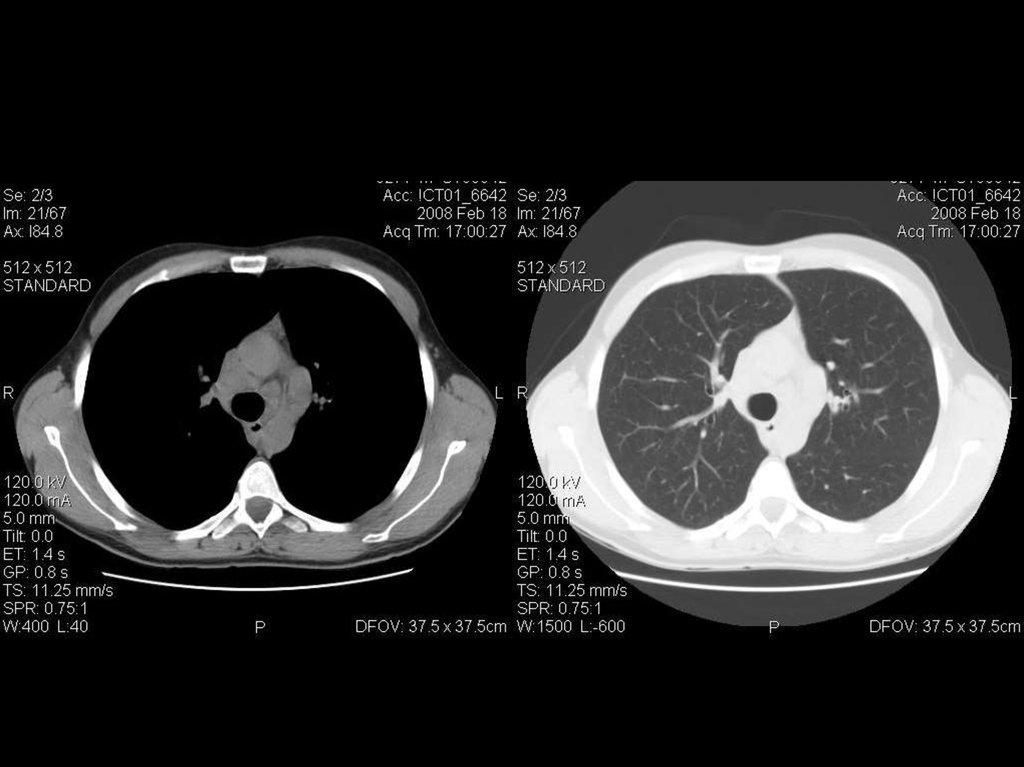

исследование лёгких

исследование брюшной полости

Ток: 300 мА

Напряжение: 120кВ

Толщина среза: 5.0 мм

Матрица: 512х512

Режим: спиральный, 11.25 мм/с